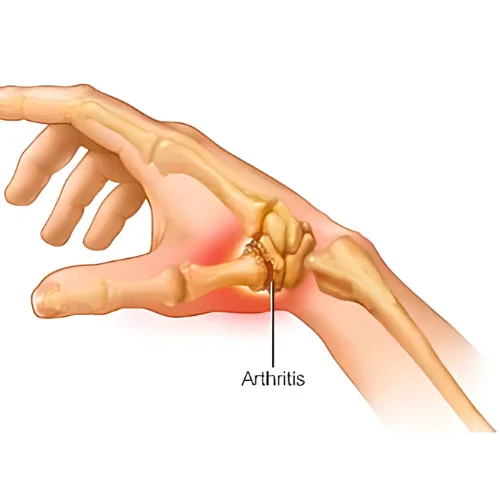

Hand and wrist surgery focuses on the diagnosis, treatment, and rehabilitation of conditions affecting the hand, wrist, and forearm. Whether caused by injury, arthritis, or repetitive strain, our expert orthopedic surgeons provide advanced surgical and non-surgical solutions to restore function, alleviate pain, and improve mobility.

This type of surgery, also called arthroplasty, is used in cases of severe hand arthritis. It is done by replacing a joint that has been destroyed by arthritis or injury with an artificial joint. This artificial joint may be made of metal, plastic, silicone rubber, or your own body tissue, such as a tendon.

Reduces or eliminates chronic joint pain.